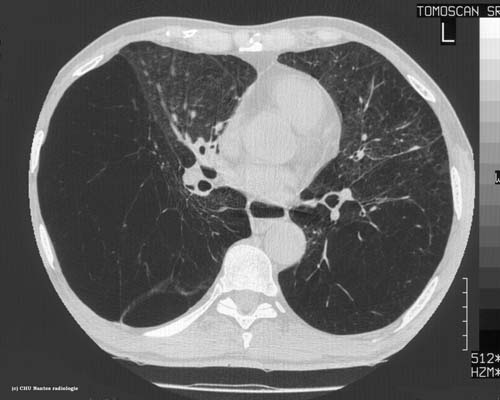

Emphysème pulmonaire sévère